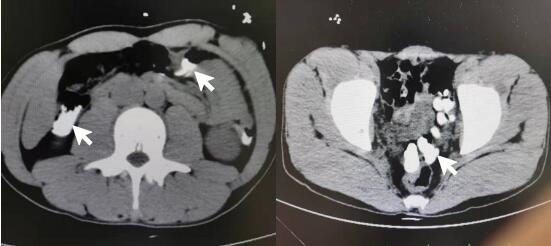

患者男性,24岁,工人,因感情问题情绪失控后口服磷酸铵盐灭火剂,未混合其他液体,干粉直接吞服,具体剂量难以准确估计,数分钟后出现呕吐伴口咽部疼痛。约3h后到达外院洗胃,洗出大量黏稠浑浊液体。后留置胃肠减压,缓慢引流出灭火剂混合淡褐色胃液。胃液隐血++,血白细胞21.1×109/L,肌酸激酶2 006 U/L,动脉血气分析pH 7.26,标准碳酸氢根15.1 mmol/L,碱剩余-12.4 mmol/L,血钾5.6 mmol/L,血钙1.06 mmol/L。立位腹部平片及胸部CT平扫见胃腔内大量高密度影(见图 1)。外院给予护胃、纠正酸中毒及补液对症治疗,后转至本院进一步就诊。

图 1 患者外院立位腹部平片和胸部CT平扫示胃腔内大量高密度影